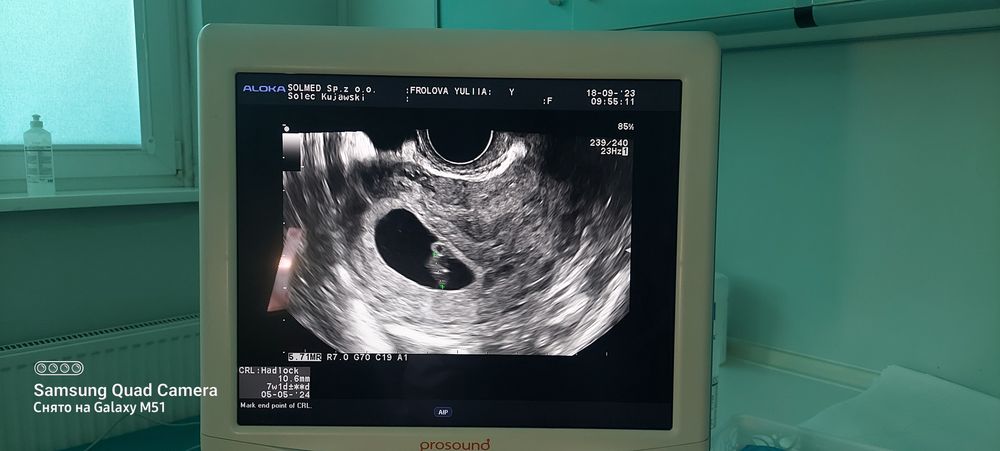

Юлия Перминова 2 года Мой малышунчик 10.6 мм 9 акушерских недель. Дату пдр поставили на 5 мая. Посмотрите еще 20 записей на эту тему Лучший ответ Юлия Перминова Судя по дате пдр то Малышок соответствует сроку 7.1 нед. 18.09.2023 Ответить Отменить Ответить Результаты анализов не радуют Тест на переносимость глюкозы Чаты Беременных Выберите чат: Январята-2026 Февралята-2026 Мартята-2026 Апрелята-2026 Майчата-2026 Июнята-2026 Июлята-2026 Августята-2026